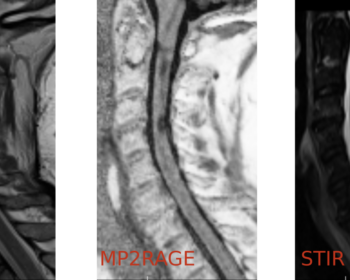

“Multiple Sclerosis Spinal Cord Lesion Detection from MultiSequence MRIs”   An uncommon but relevant task: spinal cord lesion detection Multisequences: 4 sequences potentially available with various resolutions Missing modalities: all four sequences not available for each patient at training and at testing   Challenge Rationale Lesion detection: Let’s not forget the…